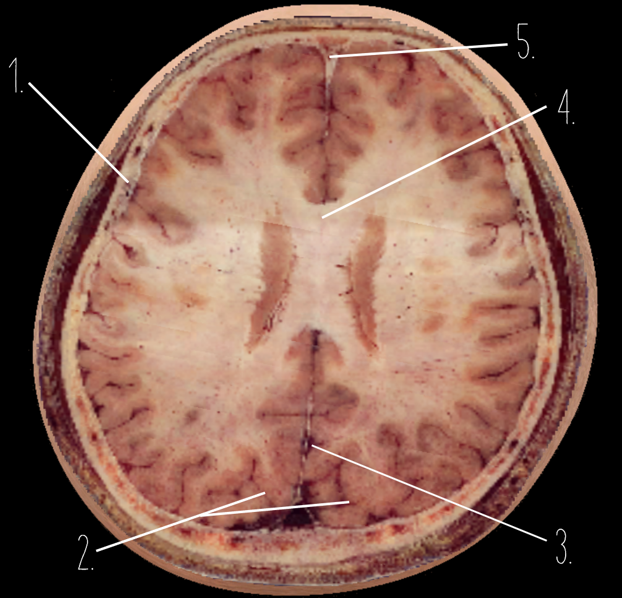

1

Frontal Bone

2

Frontal Lobe

3?

Falx Cerebri

4?

Gray Matter

5?

White Matter

6?

Sulcus

7?

Gyrus

8?

Fissure